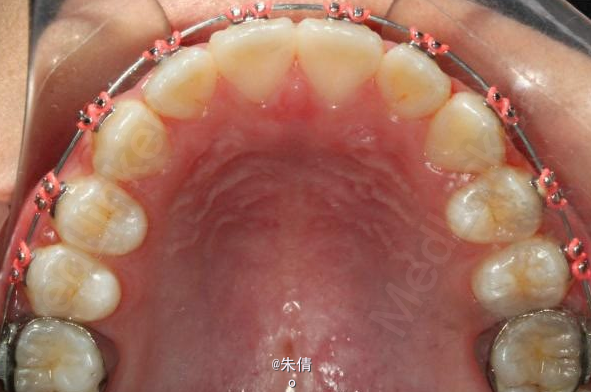

对于面型较好,拥挤度不大的病例,推磨牙向后不失为一种很好的方法,当然现在推磨牙后向的手段和方法很多,但是主要 是适应证的问题。我认为我们在做推磨牙向后,首先是考虑拥挤度,第二个要考虑的是现有的面型,第三点也是很重要的一点,是考虑牙弓后段拥挤度,Tweed-Merryfireld拥挤度的诊断方法将牙弓拥挤度分析分为三段,牙弓前段拥挤度,牙弓中段的拥挤度,以及牙弓后段的拥挤度。不管用什么方法或是手段推磨牙向后,一定不能将牙弓前端矛盾移到牙弓中段或是后段。今天给大家看一直面型,拥挤度不是很大推磨牙向后的病例。希望对大家能有所帮助。